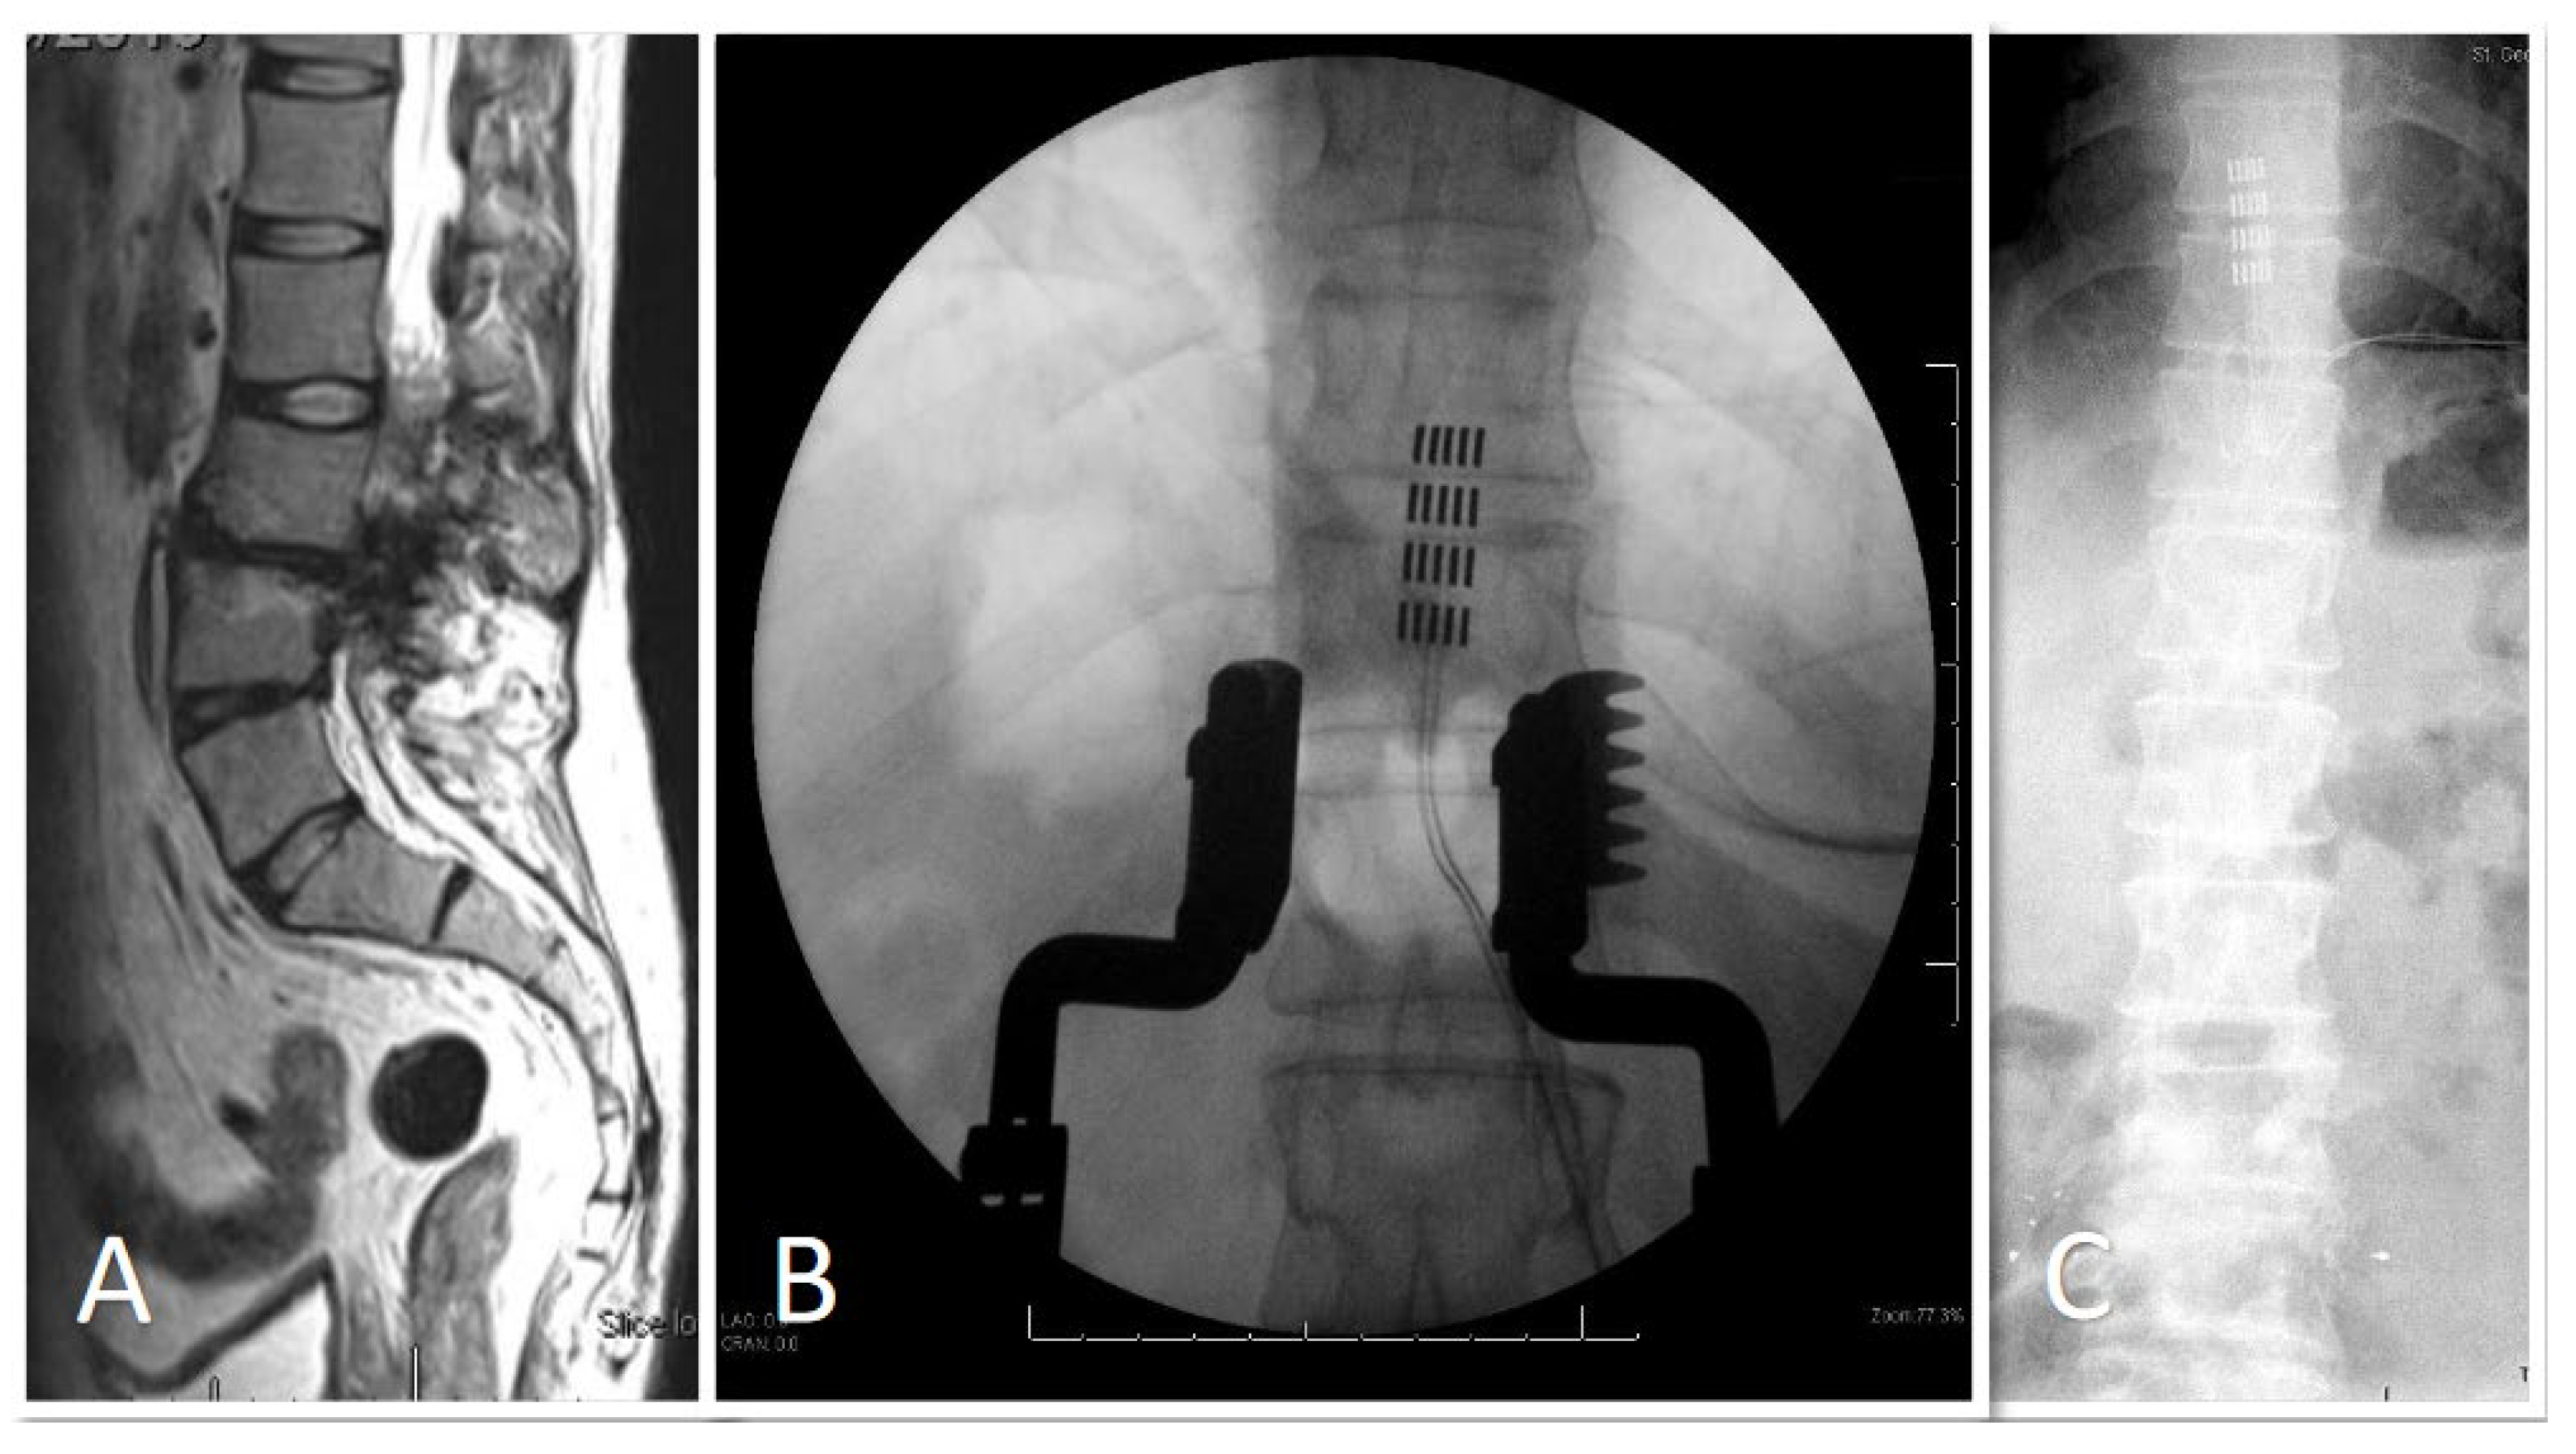

3. Results

3.1. Demographic and Clinical Data